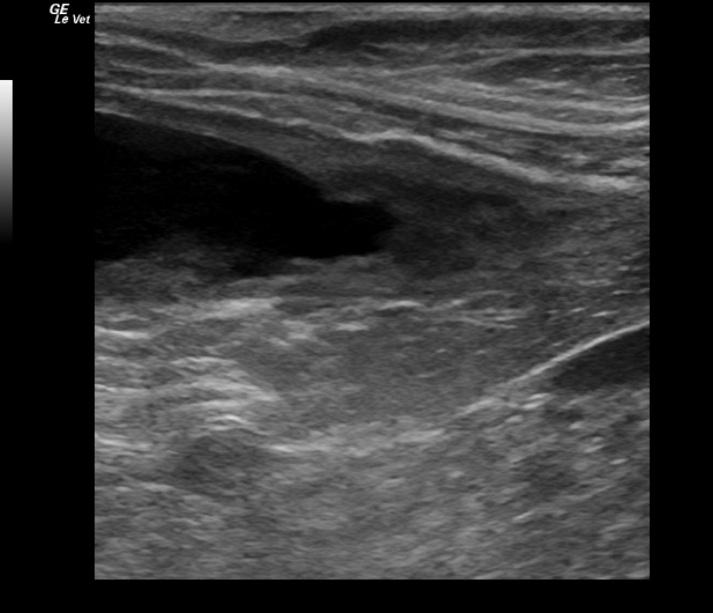

An 11-year-old spayed female German Shepherd dog was presented for leaking urine. On physical examination, the patient was quiet, alert and responsive, and had matted, wet hair on the vulva. Abnormalities on urinalysis included proteinuria, 3+ hematuria, leukocyturia, cocci bacteria, a few triple phosphate and amorphous urate crystals. Urine culture yielded coagulase positive Staphylococcus spp. Urine microalbumin was markedly elevated. The patient was treated with Clavamox, but was presented several days later for ongoing leaking of urine. Physical examination and survey abdominal radiographs were both within normal limits. The patient was treated with Simplicef and Rimadyl.